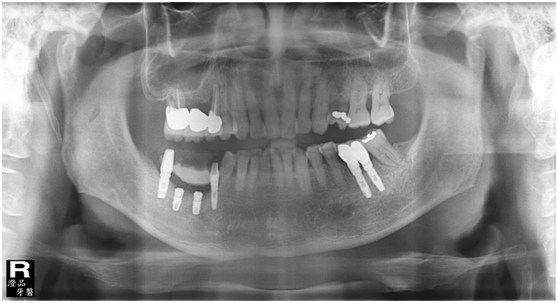

直到經過一年半後,於99/07/19又有明顯發炎,拍攝追蹤片,發覺連同更遠心的那顆植體的骨頭也破壞下降了

99/07/19

和患者積極溝通,由於患者神經管上的骨高度並不理想,建議積極移除中間兩顆有問題的植體重放,阻止發炎與骨破壞繼續下降;但患者想再追蹤。

患者於99/10期間因起床後有暈倒現象,住院後持續吃抗凝血劑,雖有發炎但不致於不舒服,因此一直不願積極處理;終於在100/03/1將兩顆植體移除,並於100/05/23回診評估再次植牙的條件。

100/05/23

於100/06/07重新放置兩顆植體

並於100/10/25將中間兩顆植體做二階接出

由於前後植體的高低差距太大,決定將中間兩顆高度較為一致的植體假牙做連結,但前後兩顆做單顆假牙的設計。

100/11/21 補綴完成

目前植體周圍的組織都很理想健康並追蹤中。

a. 右下第一小臼齒的植體位置,放置得太低;若能將此顆植體上的polished surface放在骨平面上,應可減少之後將鄰近植體骨高度往下帶的情形。

b. 近遠心間距在植體間的間距需求為2-3 mm(指最終第一小臼齒植體與鄰近植體間距),比當初第一小臼齒尚未拔除時,是自然牙與植體的間距需求更大(最少為1.5mm);因此造成骨破壞的因素之一,也可能和鄰近植體的間距不足有關。

由以上案例可以了解,當一個植體的位置不佳時,影響到的將不只是這顆牙將來的問題;原本7年沒有臨床症狀的鄰近植體,也被牽連並重新治療。